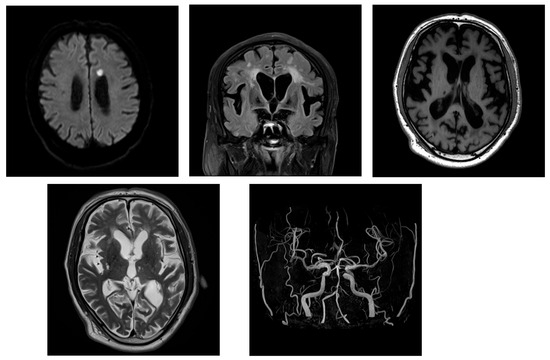

2.2. Case 2